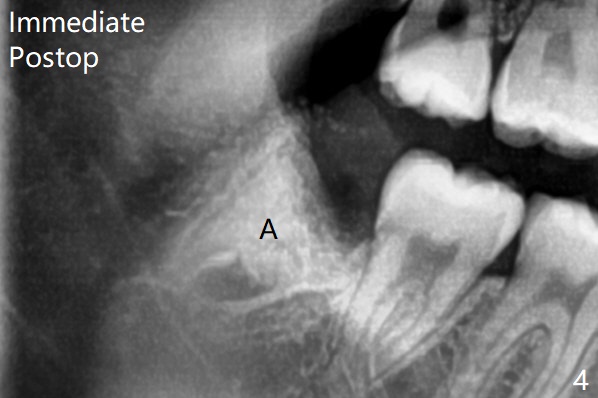

18岁时三角形变大,密度增高(图二)。其实术中发现外斜嵴两侧都不明显(女孩原因?),拔除两侧都需要颊侧去骨。由于左侧智齿颊侧阻生(图三:*),拔除后两侧都放置骨水泥(Bond Apatite,图四:A)促进骨修复,口腔卫生欠缺,可能容易形成牙周炎。